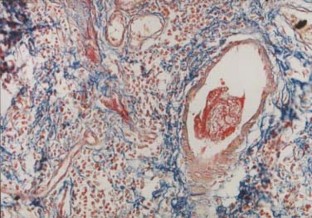

Mucosal microvacular thrombi in rectal biopsies were observed in some ulcerative colitis (UC). Heparin may be effective in steroid resistant UC in some studies, however, the new results of meta-analysis demonstrated a non-significant effect of heparin in controlled clinical trials, differing markedly from observational studies. The objective of this study was to identify colonic microvascular thrombi in larger cases with UC, and analyse its possible risk factors: age, gender, histologic score, extent of lesions and operation or biopsy specimens, and assess the significance of microvascular thrombosis in patients with UC. The microvascular thrombi were identified by immunohistochemical staining with anti-CD61 monoclonal antibody and Martius scarlet blue (MSB) staining in 40 colonic tissue samples of UC (31 biopsy specimens and nine operated cases) and 12 cases of normal colon tissue from operated colonic carcinoma. Logistic regression analysis was used to assess the relationship of age, gender, degree of histology, origin of the specimens, extent of lesions and microvascular thrombi examined. Microvascular thrombi were positive in 14 of 40 UC cases, and none in the controls. The presence of microvascular thrombi was related to operation specimens with odds ratio 11.667, P=0.0179, it might be also related to histologic score (OR=1.350) and extent of lesions (OR=1.619). These results suggest that microvascular thrombosis may be one of the important pathogenesis in some UC, and that the effect of anticoagulant treatment still needs to be assessed.

Fig. 1

Fig. 2

Fig. 3

Fig. 4